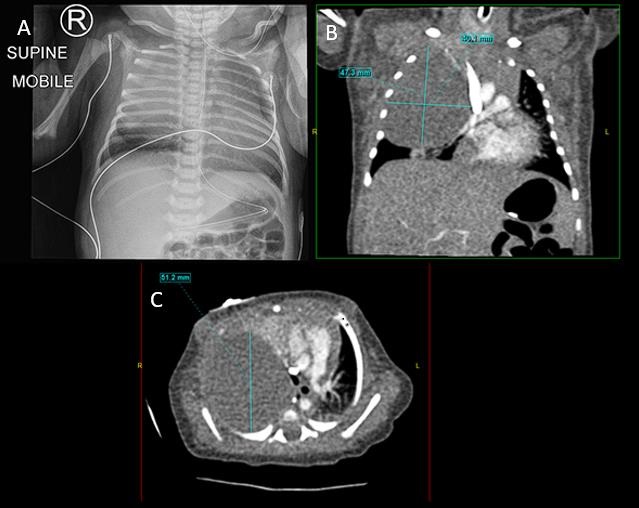

Figure 2

(A) Chest X-ray of Case 2 on Day 1 of life showing a homogenous opacification of the right middle and upper zones. (B) Coronal view of CT chest with a contrast of Case 2 on Day 2 of life showing a large low-density lesion in the right upper hemithorax which was not typical of CPAM and suggestive of a congenital lung tumor (C) Axial view.

A female twin was born at 35+5 weeks gestation via elective cesarean section. Apgars at birth were 7 and 9. She had normal antenatal scans. After birth, she developed respiratory distress and was transferred to our institution. She was initially managed with CPAP but required intubation on day 2 of life. Chest x-ray (Fig. 2) showed a homogenous opacification of the right middle and upper zones. CT chest with contrast (Fig. 2) showed a large low-density lesion in the right upper hemithorax which was not typical of CPAM and suggestive of a congenital lung tumor.